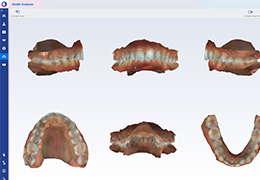

ANYTHINK 经导管主动脉瓣膜置换术分析系统